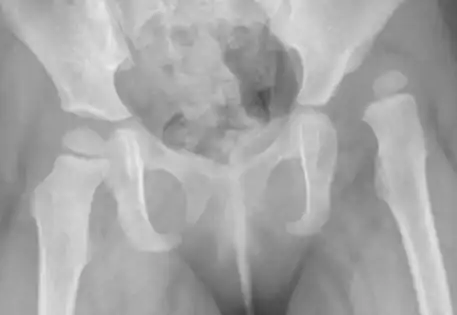

Clinical Case A : 2 year old girl presenting with left dislocated hip

According to the International Hip Dysplasia Institute, one in five hundred children is born with a dislocated hip. Although some will be diagnosed at birth, many will evade clinical detection and present when the child is walking age and a painless limp or asymmetry in the legs is noted. In children older than six months, an X-ray is a better investigation than an ultrasound to diagnose hip dysplasia.